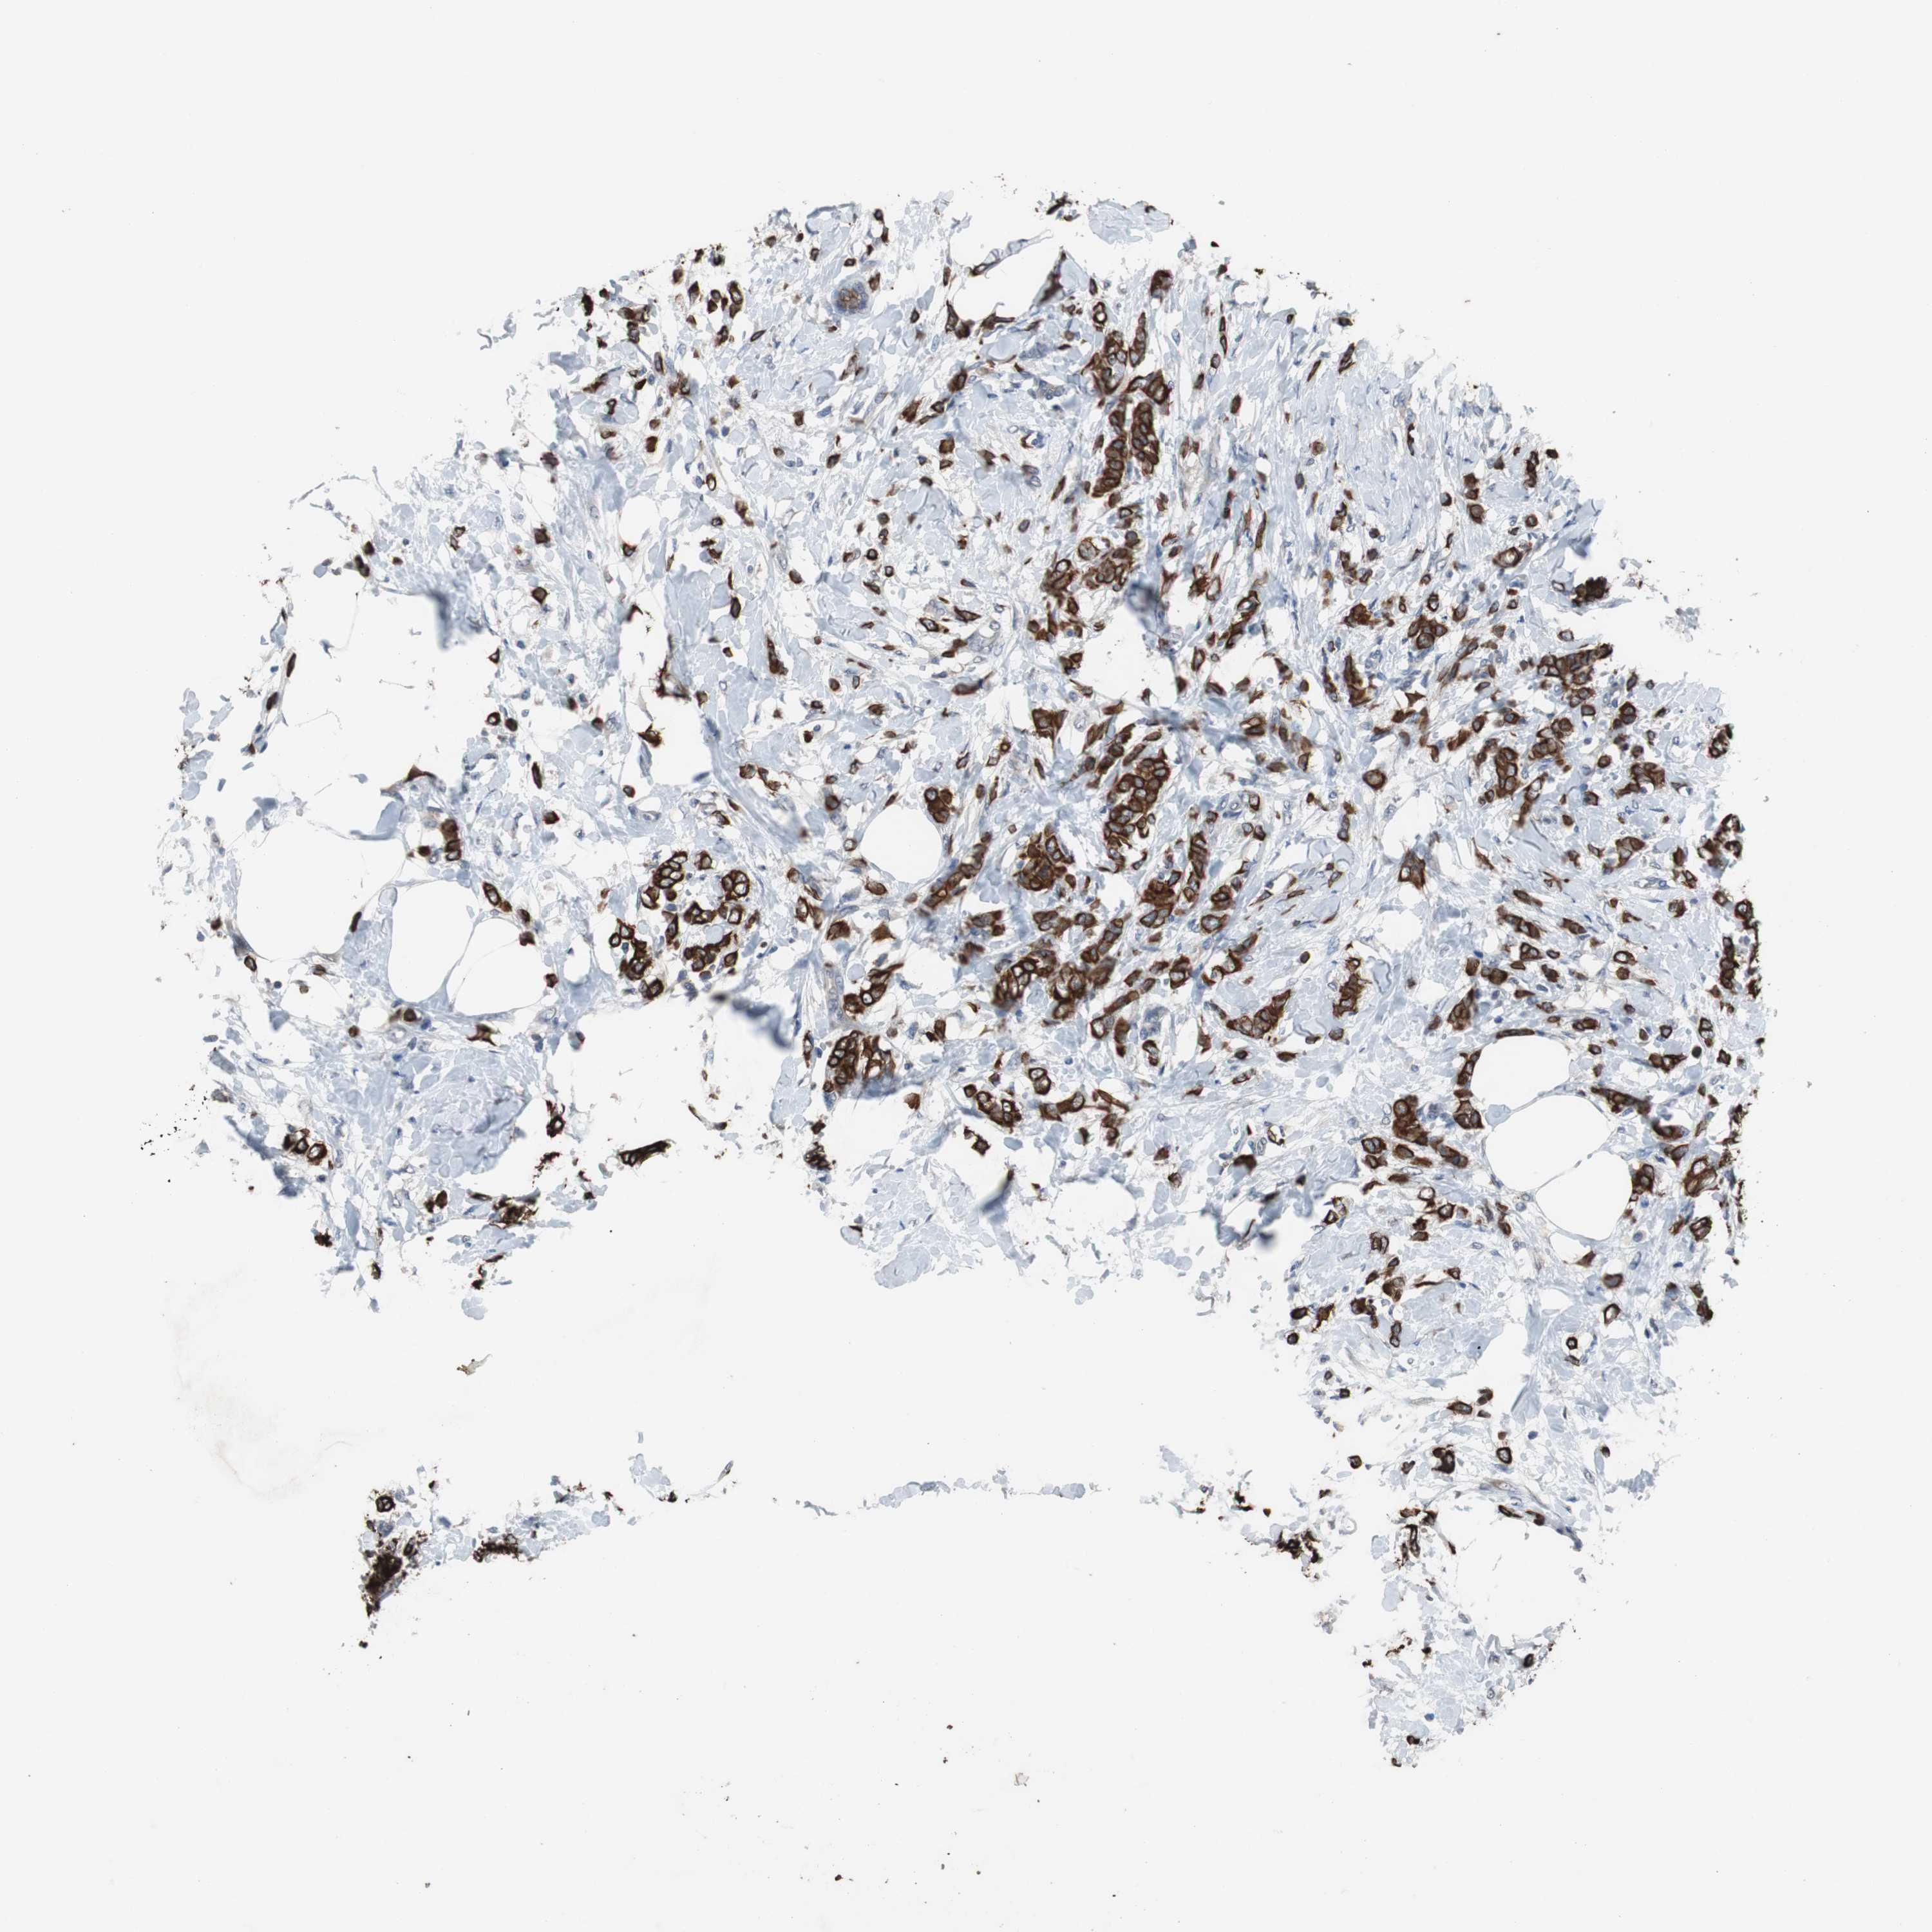

CANCER BREAST CANCER Show tissue menu

BRCA TCGA BRCA VALIDATION PROTEIN EXPRESSION

ANTIBODIES

AND

VALIDATION